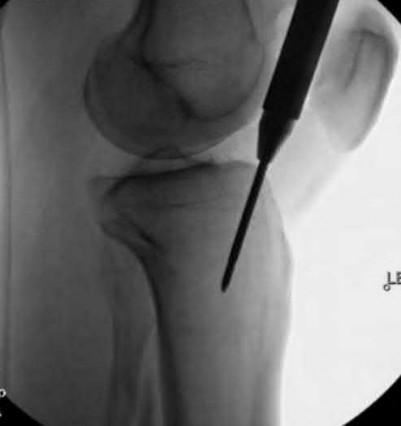

Question 16

During a posterior-stabilized total knee arthroplasty, the surgeon evaluates the gaps using trial components.

The assessment demonstrates that the extension gap is perfectly balanced and rectangular, but the flexion gap is excessively tight. What is the most appropriate isolated next step to balance the knee?

If the flexion gap is tight but the extension gap is balanced, the surgeon must alter the flexion gap without affecting the extension space. Downsizing the femoral component (using the same posterior referencing guide, or using an anterior referencing system) translates the posterior condylar surface anteriorly, effectively increasing the flexion space while leaving the distal femoral resection (extension gap) unchanged.